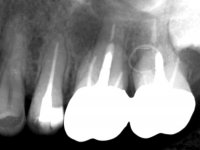

Male patient, 34 years old, non-smoker. Teeth 17 and 16 had extensive restorations with composite resin and placed intra-radicular posts. In the imaging examination, it was found that the endodontic treatment was not technically satisfactory, but had been asymptomatic for several years. The patient was rehabilitated with a 2-element bridge at 17 and 16 and 4 years later an abscess appeared in the apical area of 2.6. It had the 2.8 tooth included with a close relationship with the 2.7 root. During these 4 years there was no positional change of this tooth. After endodontic retreatment of teeth 27 and 26, an abscess appears again in the area of tooth 26, possibly associated with a root fracture. Given the history referred to in relation to tooth 26, it was considered a tooth with indicated extraction.

Teeth 17 and 16 were prepared for the fabrication of a 2-element Zr bridge. The impression was performed with a double mixing technique and a monolithic bridge in Zr was made in the laboratory. 4 years later, an abscess appeared in the apical area of tooth 26. It was decided to remove the bridge, remove the intra-radicular posts and retract the endodontic treatments of teeth 17 and 16. The removal of the bridge was carried out by making two cervical cavities. in the palatal area of the bridge and with a microluxator, disinsertion movements were performed. The intra-radicular posts were removed using fine drills and an ultrasound tip. The bridge was provisionally cemented and the patient was referred to a fellow endodontist for endodontic retreatment. After the retreatment, the intraradicular posts were placed again and the bridge was definitively cemented. One year later, a new abscess appears, possibly related to a root fracture. The bridge was sectioned between tooth 27 and 26 and tooth 26 was extracted and the crown of 27 was provisionally cemented. 3 months later, teeth 27 and 25 were prepared and a temporary bridge was made in dual polymerization resin. Then, an impression was made using the double mixing technique and a 3-element bridge in Zr was made in the laboratory. It was permanently cemented in the mouth with resin-reinforced glass ionomer cement.